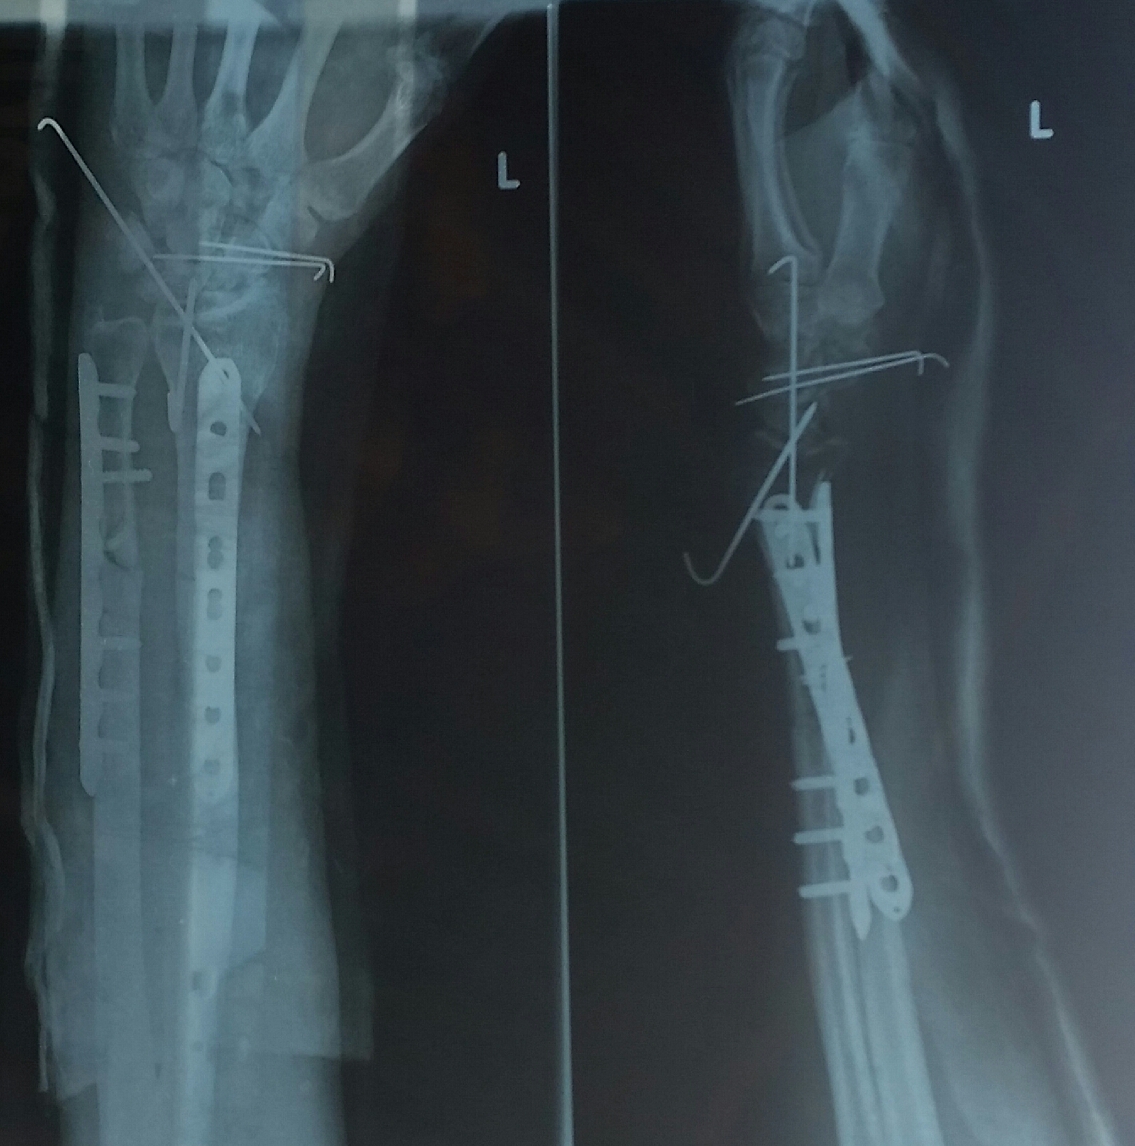

Медицинские снимки: Пластина в левом предплечье